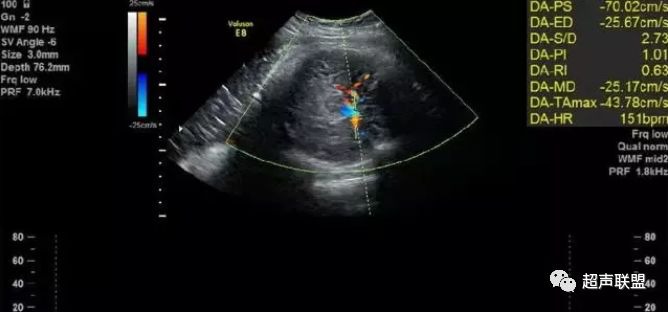

图3 正常大脑中动脉血流频谱

图4 大脑中动脉血流阻力减低